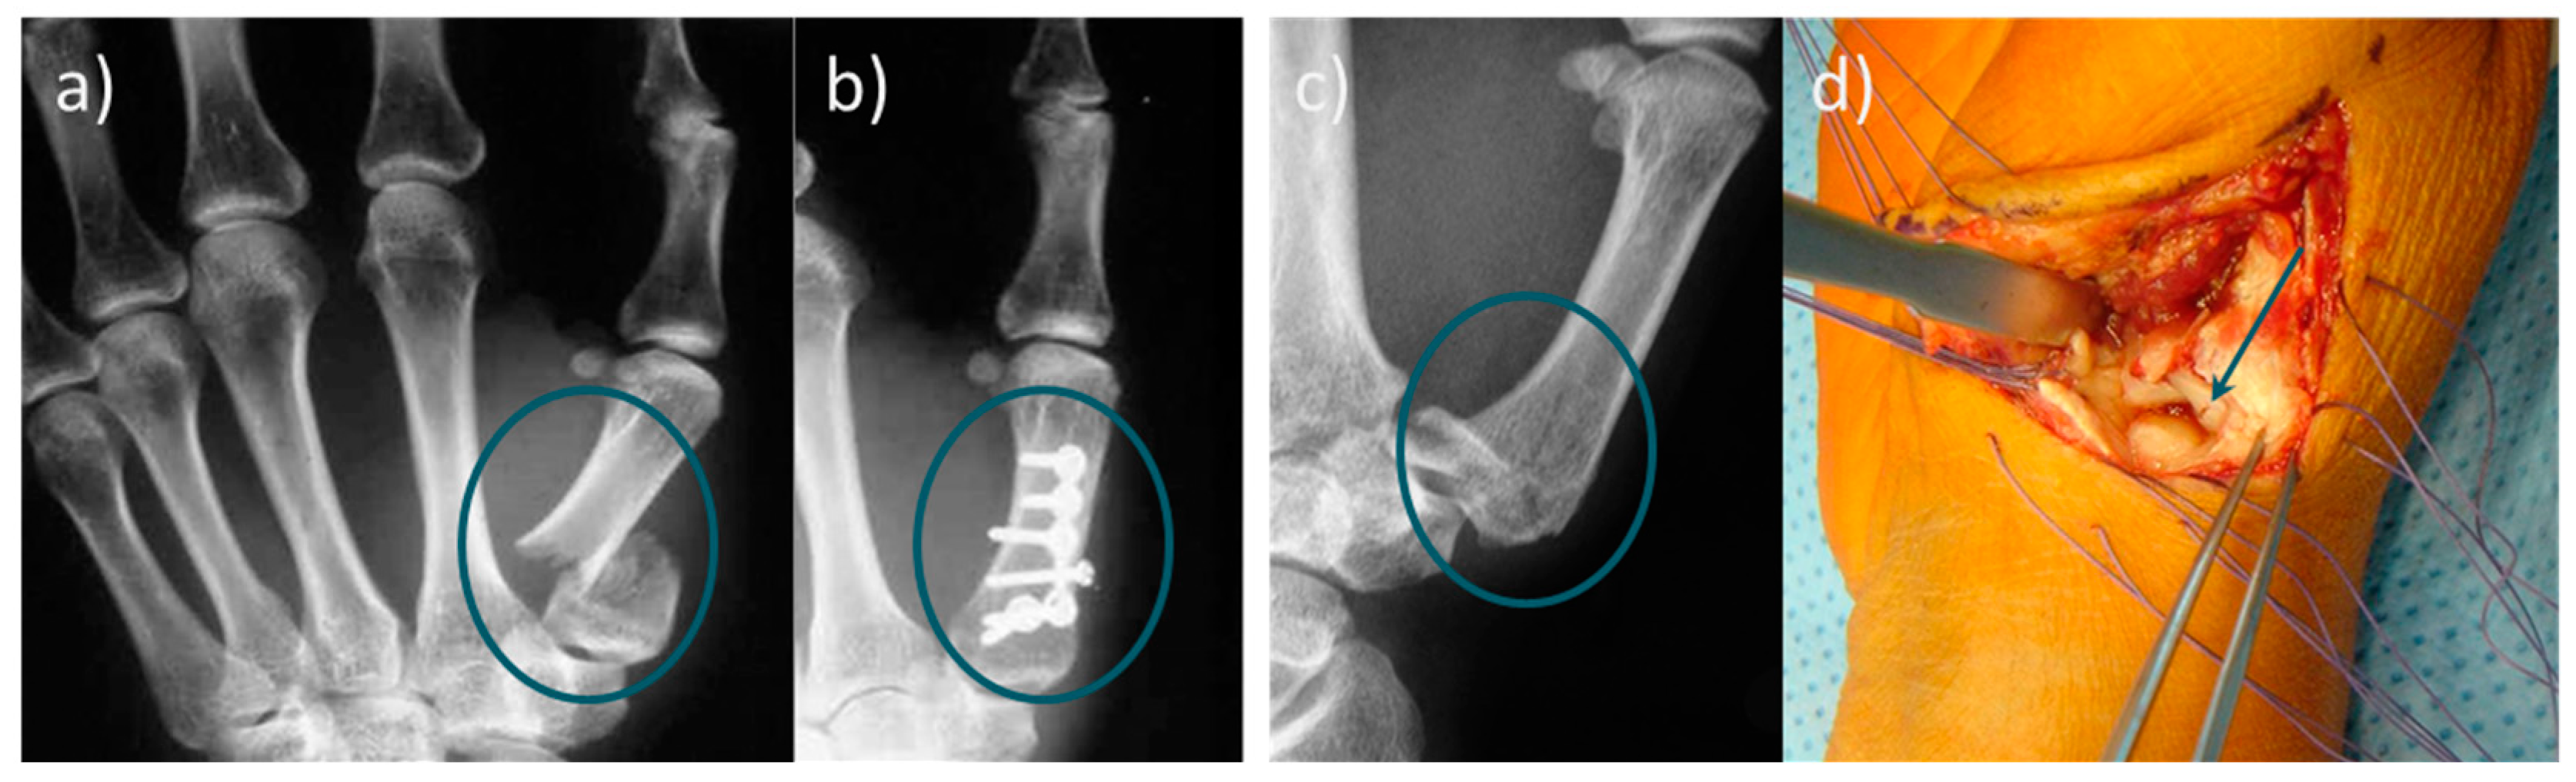

In summary, treating bone fractures with bone adhesives would be an attractive alternative to metallic implants [24], especially for small fragment fractures like basal fractures of the thumb or Rolando fractures (Figure 1), debris fractures, and low-stressed bone regions. Bone adhesives have the potential to shorten the treatment time and partially eliminate subsequent treatments. Taken together, there is a high clinical demand for bone adhesive bonding technology.

Figure 1. (a) Radiograph of a basal fracture of the thumb. (b) Conventional osteosynthesis of the basilar fracture; (c) radiological image of a Rolando fracture, and (d) representation of the small bone fragments in the joint area, which can only be fixed unsatisfactorily by classical osteosynthesis. Refixation of metacarpal fractures is usually complicated and time-consuming. Since limitations of conventional osteosynthesis exist, the use of bone adhesives would be particularly useful in the metacarpus area.